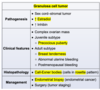

what is the finding

what disease is this finding associated with

thymoma (an anterior mediastinal mass)

-Myasthenia Gravis: will present with dysphagia and unable to swallow = bulbar dysfunction

what is the pathiphysiology of myasthenia gravis

autoAb from the thymus against n-Ach R in the neuromuscular junction –> impaired action potential at receptors –> M wkness

will have weakness that is worse throughout the day, often presents with fatiguable chewing or dysphagia